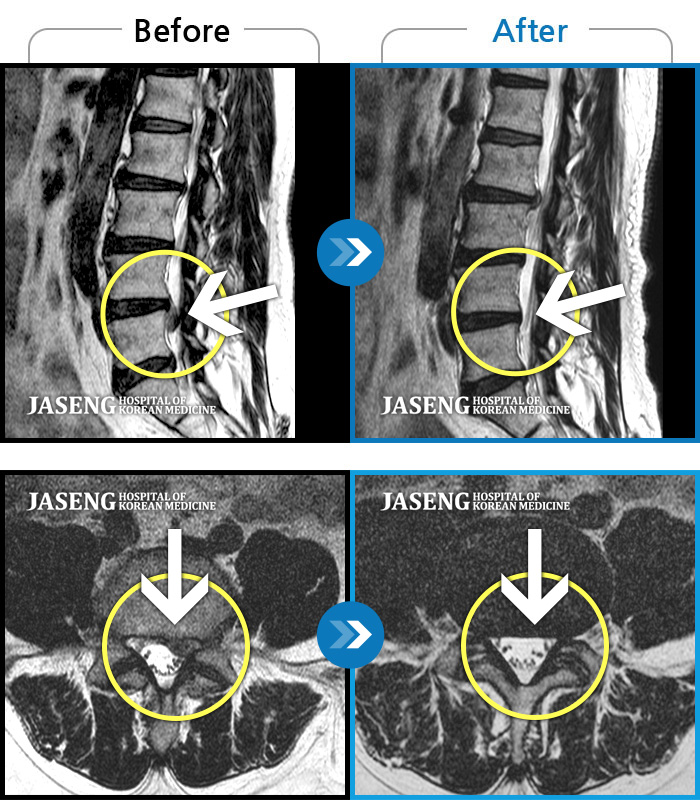

MRI 치료사례

2023.12월경에 눈길에 걷다가 삐끗한 후 발생한 허리 통증으로 오신 분입니다.